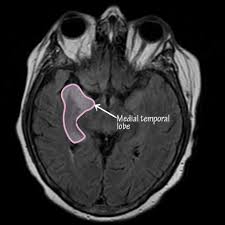

Lesions similar to cytotoxic edema, and lesions similar to vasogenic edema. Seizure, altered sensorium, fever frontal and temporal lobes, rarely extratemporal t2 hyperintensity, restricted diffusion, sometimes. Herpes encephalitis is the most common sporadic encephalitis in the united states and other industrialized countries .occurring as either a primary infection with herpes simplex virus or as a reactivation of latent virus, herpes encephalitis causes significant morbidity and mortality .early intervention with acyclovir significantly improves outcome; The clinical syndrome is often characterized by the rapid onset of fever, headache, seizures, focal neurologic signs, and impaired consciousness 1 . Having said that, mri with contrast is considered the most sensitive imaging modality, and findings are present in over half of individuals 8. The patients with the former type of lesions had fulminating disease, and were in severe clinical condition. Herpes simplex encephalitis occurs as 2 distinct entities: 4 it was found that, rather surprisingly, varicella zoster virus (vzv), the cause of chickenpox and herpes zoster, was the most frequently detected virus at 29%, with hsv and enteroviruses accounting for 11% of cases. Two subtypes are recognized which differ in demographics, virus, and pattern of involvement. (1)department of radiology, ankara numune education and research hospital, ankara, turkey. Neonatal herpes simplex encephalitis is caused by vertical transmission of infection during passage from birth canal with diffuse cerebral involvement within the first month after birth; As the older term limbic encephalitis implies, the most common location of involvement is the mesial temporal lobes and limbic systems, typically manifested by cortical thickening and increased t2/flair. In patients with herpes encephalitis, two distinct types of diffusion imaging findings (on b =1000 s/mm 2 images, and adc maps) were noted:

For viral infection of the meninges, please refer to the general article on viral meningitis, and, for a broad view on the curriculum of infections of the central nervous system, refer to cns. Two subtypes are recognized which differ in demographics, virus, and pattern of involvement. A recent study in finland also used pcr to detect various viruses in the csf of over 3000 patients who had infections of the cns including encephalitis, meningitis, and myelitis. The patients with the former type of lesions had fulminating disease, and were in severe clinical condition. Despite advances in antiviral therapy over the past 2 decades, herpes simplex encephalitis (hse) remains a serious illness with significant risks of morbidity and death. Normal mr imaging findings (type 1, 53% of patients), isolated hippocampal involvement (type 2, 13%), other brain lesions without hippocampal involvement (type 3, 13%), and other brain lesions with hippocampal involvement (type 4, 21%). Lesions similar to cytotoxic edema, and lesions similar to vasogenic edema. As the older term limbic encephalitis implies, the most common location of involvement is the mesial temporal lobes and limbic systems, typically manifested by cortical thickening and increased t2/flair.

The patients with the former type of lesions had fulminating disease, and were in severe clinical condition. The diagnosis of hse is based on laboratory investigations, magnetic resonance (mr) imaging findings, electroencephalogram and, occasionally, a biopsy. Herpes encephalitis is the most common sporadic encephalitis in the united states and other industrialized countries .occurring as either a primary infection with herpes simplex virus or as a reactivation of latent virus, herpes encephalitis causes significant morbidity and mortality .early intervention with acyclovir significantly improves outcome; Herpes simplex (hsv) encephalitis is the most common cause of fatal sporadic fulminant necrotising viral encephalitis and has characteristic imaging findings. In patients with herpes encephalitis, two distinct types of diffusion imaging findings (on b =1000 s/mm 2 images, and adc maps) were noted: Relapse of encephalitis occurs in up to 10% of patients, manifested by recurrent symptoms, clinical and mri findings, and the presence of herpes simplex virus type 1 dna in the cerebrospinal fluid (csf). In children older than 3 months and in adults, hse is usually localized to the temporal and frontal lobes and is c. In patients with herpes encephalitis, two distinct types of diffusion imaging findings (on b =1000 s/mm 2 images, and adc maps) were noted: Herpes simplex (hsv) encephalitis is the most common cause of fatal sporadic fulminant necrotizing viral encephalitis and has characteristic imaging findings. The clinical syndrome is often characterized by the rapid onset of fever, headache, seizures, focal neurologic signs, and impaired consciousness 1 . We present mri findings of two cases of herpes simplex encephalitis (hse) confirmed by pcr analysis, focusing on the serial changes after acyclovir therapy: Two subtypes are recognised which differ in demographics, virus, and pattern of involvement. Despite advances in antiviral therapy over the past 2 decades, herpes simplex encephalitis (hse) remains a serious illness with significant risks of morbidity and death.